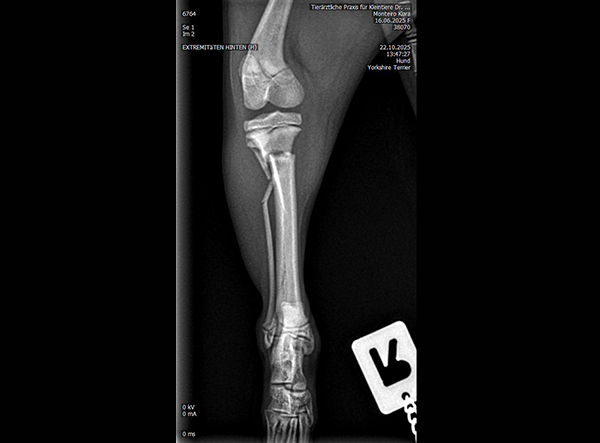

The patient, an 18-week-old female Yorkshire Terrier, was referred for surgery on October 21, 2025. The dog had sustained a fall from the owner’s arms, resulting in a fracture of the proximal tibial metaphysis just below the growth plate, along with a fibular fracture. Given the patient’s very small size and young age, precise anatomical fixation and minimal disruption of the growth zone were essential.

An open reduction and internal fixation (ORIF) was performed via a medial approach to the proximal tibia.Implant Used: 1.5 mm LeiLOX TPLO Swing Titanium Plate

The surgery was completed without complications. Postoperative radiographs confirmed anatomical alignment and stable fixation. With careful rehabilitation, the young Yorkshire Terrier is expected to regain full function and resume normal activity pain-free.